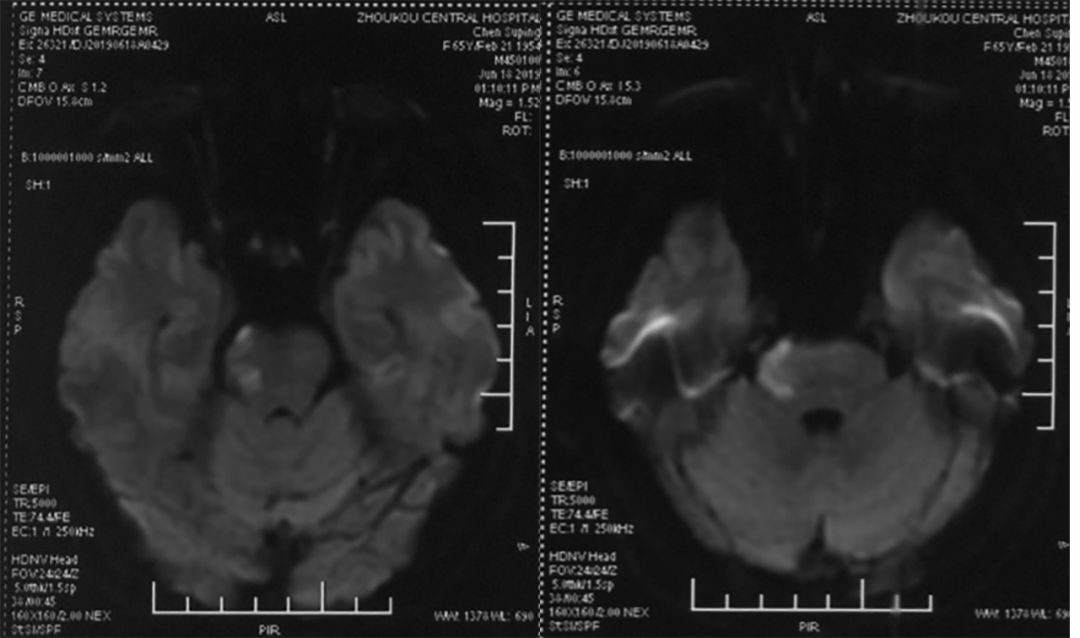

脑MRI (2019-6-18 ,*** 人民医院):右侧桥脑急性脑梗死(图1)。

图1

头MRA (2019-6-18 ,*** 人民医院):基底动脉末端动脉瘤,基底动脉中段狭窄(图2)。

图2